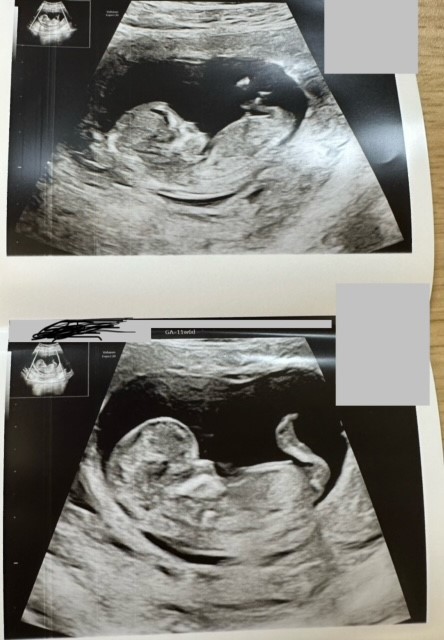

Ei näy nubia tässä kuvassaMiekin tulen kysymään osaako joku tästä meidän kuvasta jotain sanoa. Viikot 13+4. Mulla on sellainen tunne että poika tulisi, mutta tuosta nubista en osaa sanoa mitäänView attachment 138958

Ei näy nubia. Vain napanuoran alkupää näyttäisi olevan toi pätkä tossaHaluaako joku yrittää analysoida meidän bebeä? Ultran aikaan viikkoja on ollut 12+6.

Oon yrittänyt lukea nubista ja katsella erilaisia kuvia mut en nyt edelleenkään tiedä mitä kohtaa tässä pitäisi tuijotellaoltiin analysoivinamme kovastikin häntä pojaksi ultrassa mutta myöhemmin kotona tajusin, että ollaan varmaan katteltu napanuoraa koko ajan…